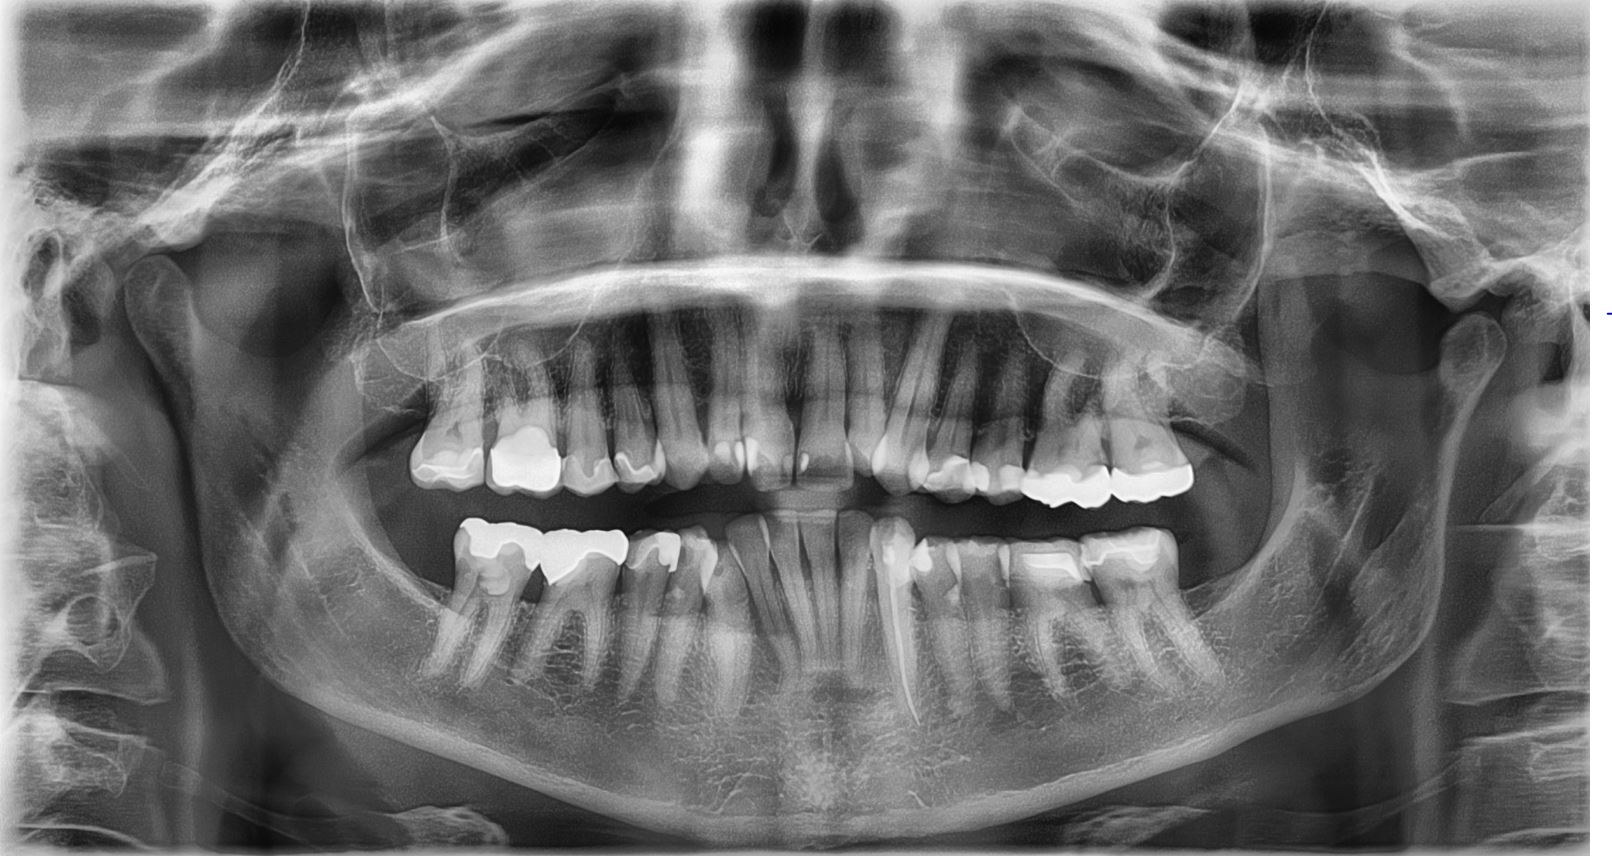

عکس دندان نوعی گراف دو بعدی می باشد که با اشعه ایکس از دندان تصویربرداری می کند. opg و سفالوگرام دو نوع عکس دندان می باشد. در opg یا عکس پانورامیک دندان نمای پانورامایی از فک بالا و پایین نشان می دهد یعنی با کمترین مقدار امواج تصویر کلی از دندان ها را ظاهر می کند در حالی که سفالوگرام ساختار های صورت و ارتباط بین دندان ها را نشان می دهد.

عکس پانورامیک دندان بدون درد می باشد، به سرعت انجام می شود و عکس ظاهر می شد. بیمار را در برابر کمترین مقدار اشعه قرار می دهد. عکس دندان اطلاعات ارزشمندی را به دندانپزشک وارتودنتیست نشان می دهد.

عکس opg به صورت گسترده در چکاپ های دوره ای معاینه دندان انجام می شود. با عکس دندان موارد زیر را می توان تشخیص داد:

- نمای کلی دندان ها

- دندان عقل نهفته

- حفرات دندانی و پوسیدگی ها

- به هم فشردگی دندان ها

- شکستگی دندان و فک

- عفونت

- تومور

- کیست های دهان و دندان

- سینوس ها

- جا به جایی

- بیماری های فک

- درمان ارتودنسی

- برنامه ریزی برای درمان همانند ایمپلنت گذاری

عکس دندان سالم

در این تصویر عکس دندان سالم را مشاهده می کنید